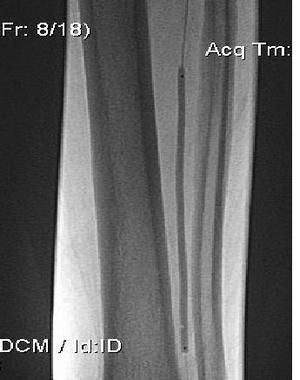

Операция

Реканализация ПББА на всем протяжении гидрофильным проводником, баллонная ангиопластика ПББА Sleek - баллоном на всем протяжении.